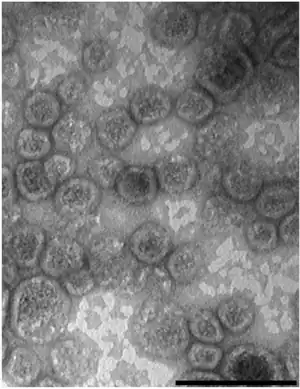

| Gram negative Shigella sonnei bacteria which spent 48 hours cultured on Hektoen enteric agar (HEK). | |